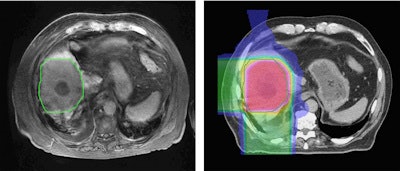

Bortfeld described a study performed at Massachusetts General Hospital in which MR images were recorded 2.5 months after five fractions of proton therapy. A reduced signal was seen in central parts of the liver. Contours of the area of signal reduction were in good agreement with the high-dose region in the treatment plan.